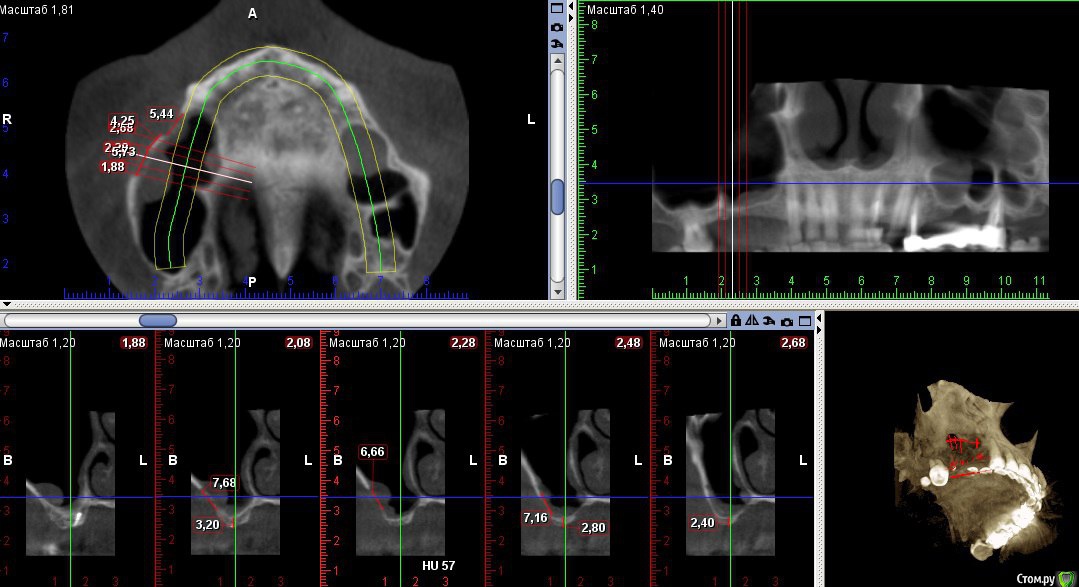

Kovalov Igor Опубликовано 19 мая, 2016 Поделиться Опубликовано 19 мая, 2016 (изменено) Здравствуйте уважаемые форумчане! Нужен совет по повторному синуслифтингу....3 месяца назад проводилась попытка синуслифтинга в 1 сегменте, отсутствие 14,15,16 зубов ... Разрез, формирование окна, в этом случае выбрал вход в синус с двух окон в проекции 14 и 16, получить перфу возле септы в области 16 когда отслаивал ... 14 отслойка без проблем... закрыл окна мембраной и ушил отправил погулять на 2,5-3 месяца.Вопрос как поступить ? Сделать одно большое окно? Как быть со спайками и как сложно их отделять ? Мембрану под перфу не подложил так как не делал ниразу этого... Кт после 3х месяцев ... Изменено 19 мая, 2016 пользователем Kovalov Igor Ссылка на комментарий

red_butler Опубликовано 21 мая, 2016 Поделиться Опубликовано 21 мая, 2016 Куда вы 2гр L сыпите та? Тромбуете штоль?Даже еще раз пересмотрел срезы, Вы считаете что на такой операционной площади и при таком строении синуса расход будет меньше? 3 Ссылка на комментарий

Kovalov Igor Опубликовано 21 мая, 2016 Автор Поделиться Опубликовано 21 мая, 2016 Даже еще раз пересмотрел срезы, Вы считаете что на такой операционной площади и при таком строении синуса расход будет меньше?Ушло 2 грамма вы правы! ))) Спасибо всем за советы , ошибки были в первом случае малое и высоко расположенное окно, сделал в этот раз одно большое окно, спайки были только по периметру окна , было ощущение что окно начало заростать костью через три месяца, будто пластинка была поверх мембраны , может показалось ...Отслаивал до септы, графт 1,5 гр. в синус и 0,5 латерально от винтов и укрыл мембраной 25*25 владмива, мембрана не понравилась если честно ) Ссылка на комментарий